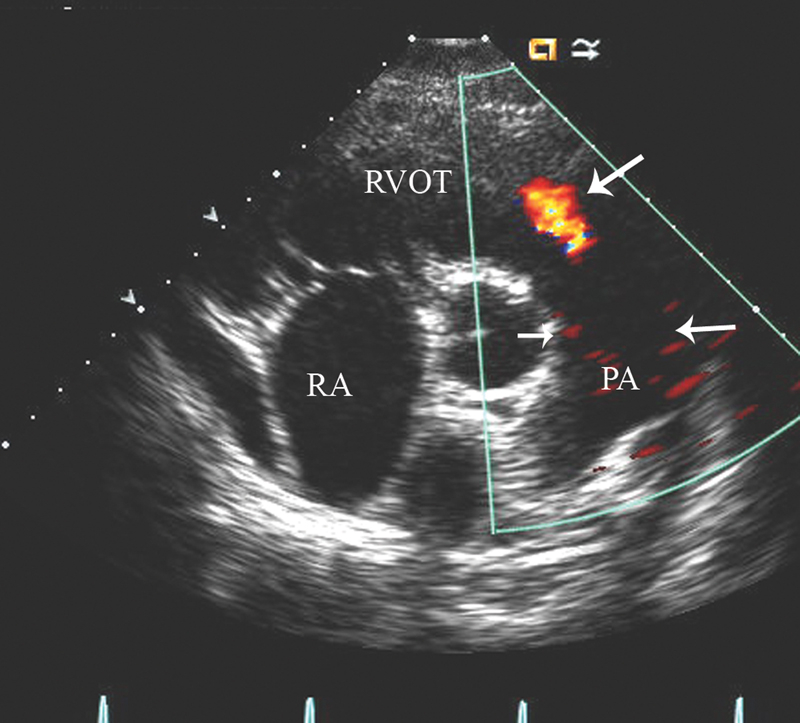

فحوصات تشخيصية لبعض امراض القلب والشرايين التاجية